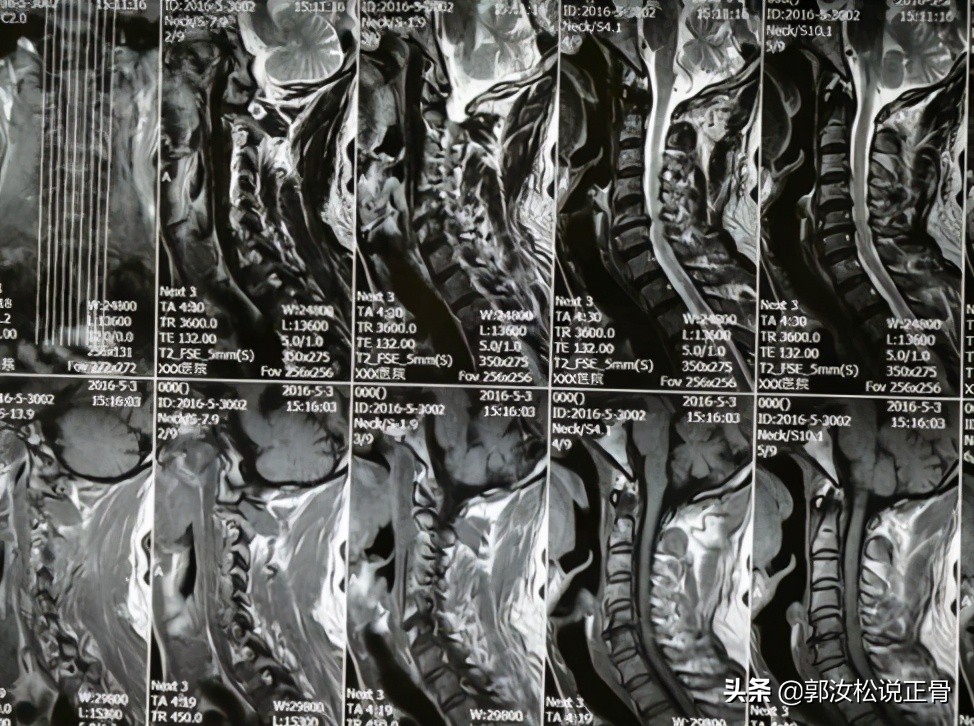

现病史: 1年前患者开始出现颈部不适,伴有头晕,发作时无天旋地转感,无恶心呕吐,无胸闷心慌,无耳鸣,走路时有不稳感,无四肢麻木,无四肢无力,随到当地医院就诊,给予颈椎MR及头颅MR检查提示:颈椎退行性变,C5/6椎间盘突出,相应层面硬膜受压,脊髓轻度受压,脊髓未见明显变性;头颅未见明显异常。当时诊断颈椎病,给予药物治疗,疗效不佳,后建议患者手术治疗,患者拒绝,随来我院我科就诊:颈部酸痛,头晕,走路不稳感,无恶心呕吐,无胸闷心慌,无四肢麻木。

/ / 诊断:混合型颈椎病 //颈椎和头颅MR